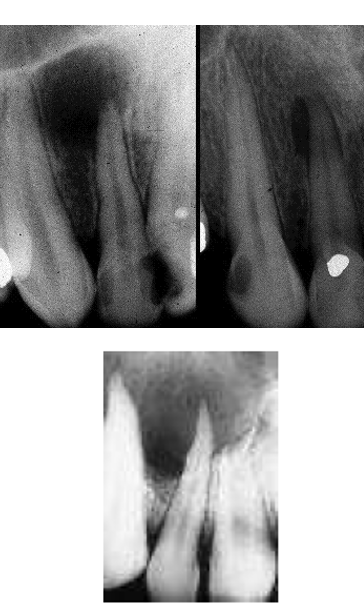

what is this

1) explain clinical

2) explain radiographic presentation

3) explain histopathology

4) explain cyst content

5) treatment

5) Treatment generally by simple enucleation & removal of assc. tooth